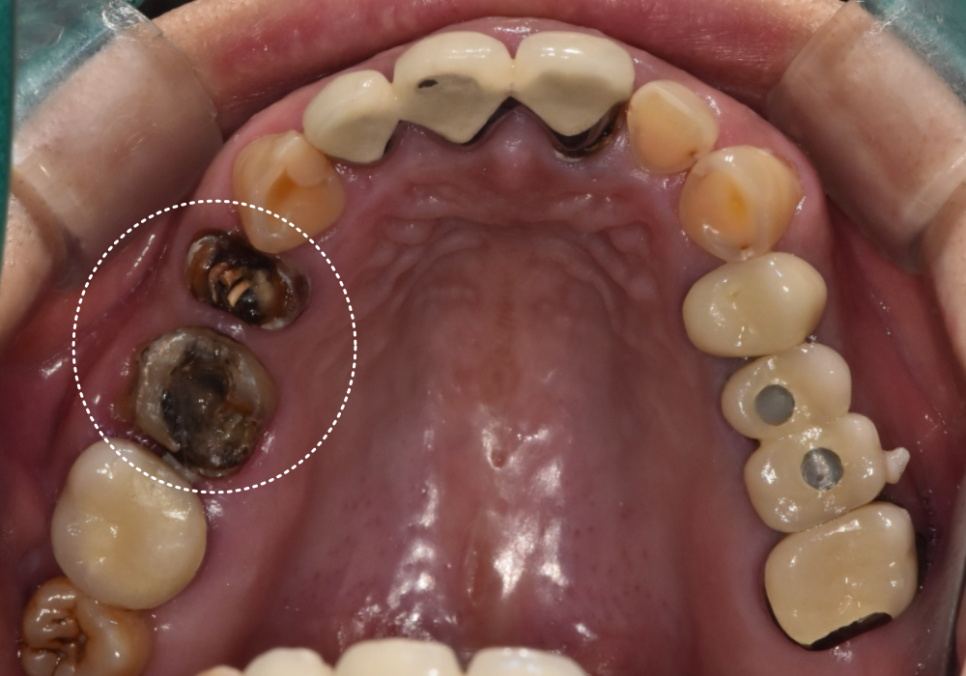

어금니도 이 상태면,

앞니도 문제 있는거 아니에요~?

어금니 쪽 내부 상태를

직접 확인하신 환자분께서는

10년 넘게 사용 중인 앞니 브릿지도

걱정이 되셨는지 여쭤보셨는데요~

입안을 살펴보니...

브릿지 경계 라인이 조금 까맣게 비쳐보이고

잇몸도 꽤 부어있는 걸 확인할 수 있었습니다.